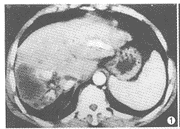

例1 男,60岁。反复发作性右上腹痛半年余。CT示肝左叶增大,右叶缩小,右叶背段见大片混杂密度区,边界欠清;增强后强化不明显,其内见斑点状及长条状结石影,左肝管及胆总管下端亦呈高密度铸形(图1),胆囊位于肝右叶后方(图2)。术后病理:(1)肝右叶胆管细胞癌;(2)肝内胆管及胆总管结石;(3)肝右叶后胆囊。

图1 肝右背段大片混杂密度区,强化不明显,左肝总管及右肝内胆管结石